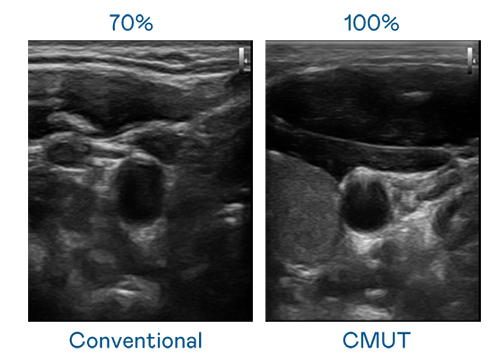

CMUT 技术是一种用电容式微机电元件来产生超音波讯号的技术。与传统 PZT 压电式技术相比,CMUT 频宽增加 30%,更宽频的超音波讯号让影像解析度大幅提升,是实现高影像品质医疗超音波扫描、促进精准医疗发展的关键技术。

超音波影像的解析度高低,首先取决于探头能发出的讯号频宽。多多28 CMUT 可提供高清晰的超音波讯号,提供高频宽、高灵敏度、影像纹理细节更高的超音波影像,协助医护人员缩短影像判读时间及利用精准的医疗影像进行诊断。